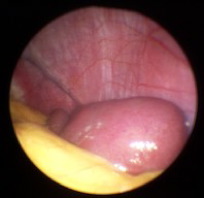

Milzbiopsie bei Sarkoidose